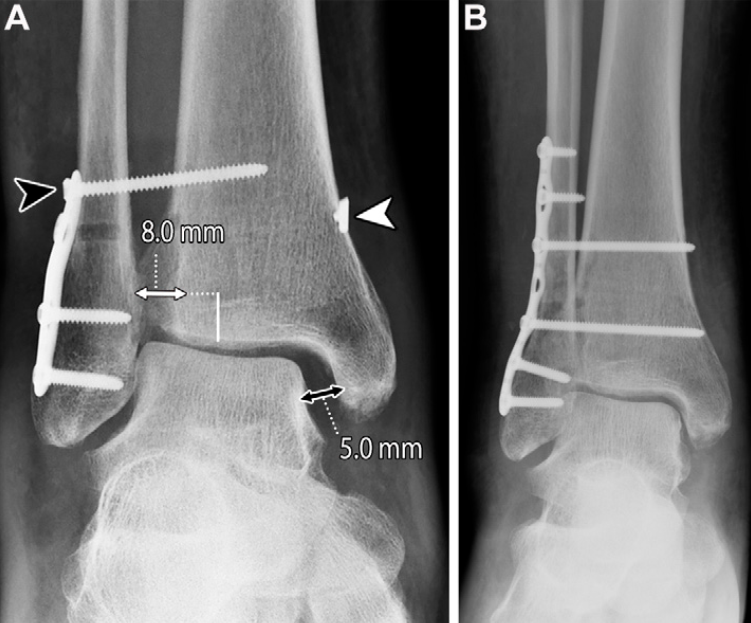

术后并发症

与术前评估相似,术后评估也主要依靠影像学表现:术后即刻影像学检查用于确认植入物位置和骨折复位效果;随访X线片则用于观察骨折愈合情况,确认胫腓联合复位的维持状态。当怀疑骨性不愈合或持续性不稳时,CT检查具有重要价值;当患者术后出现疼痛,尤其怀疑存在持续性韧带缺损和/或肌腱异常时,可采用MRI检查。约15%的患者会发生术后并发症,其中39%表现为胫腓联合愈合不良,多数病例由初始复位不足所致;4%的手术干预会发生感染并发症。

刚性螺钉固定带来的生物力学负荷,会引发多种并发症,包括胫腓联合复位不良、螺钉松动、螺钉移位和螺钉断裂,这些并发症均可能需要取出螺钉:

上述并发症可能无明显的临床症状,从而延误对疼痛性螺钉或持续性胫腓联合不稳的发现和干预。放射科医生需在影像学检查中识别这些异常并予以提示,但同时也应注意,若胫腓联合已实现良好的愈合复位,螺钉周围的松动或螺钉断裂可能无临床症状,甚至提示胫腓联合的生理活动已部分恢复。